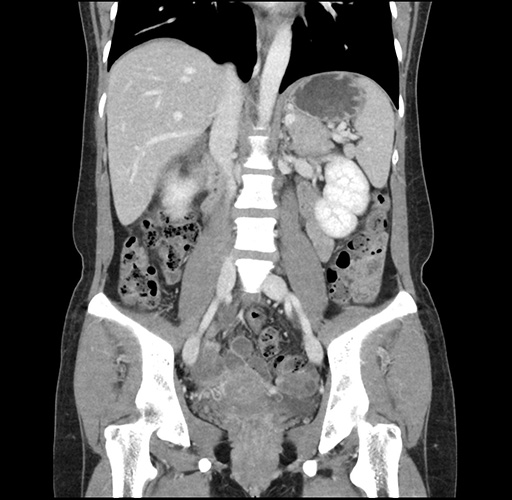

Imaging Analysis

Look through the patient's CT scan to identify any areas of concern for the necessary procedure.

Based on your CT findings, which issue(s) would give reason for "planned slowing down moment(s)" in this case?

Considering a standard left lateral sectionectomy procedure, what step(s) of the operation would you do differently in this case ?